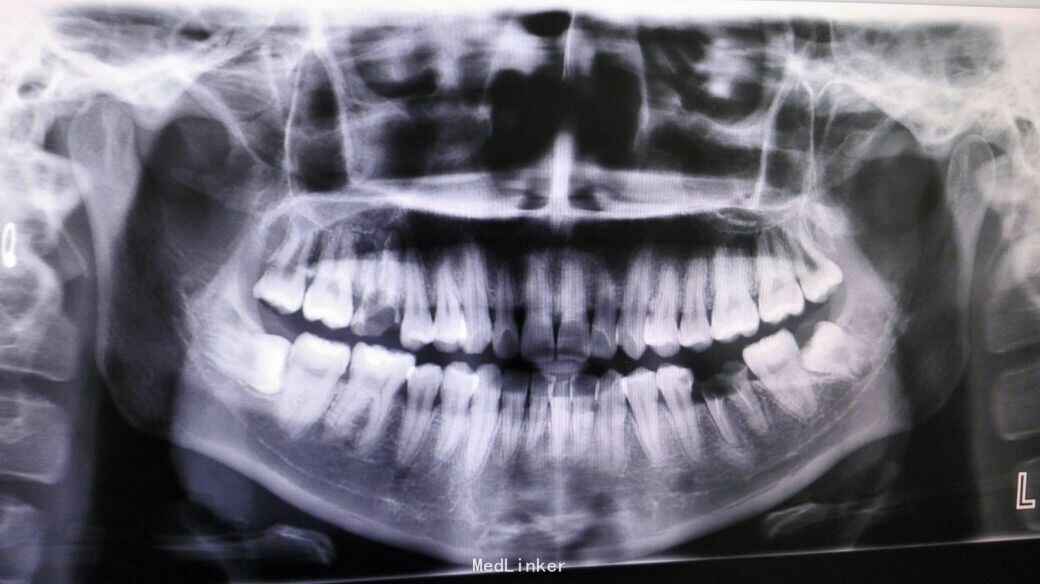

患者,男,25岁,要求拔除左下颌水平阻生牙齿,平素体质一般,无药物、食物过敏史,无高血压、心脏病等系统病史

行曲面断层片